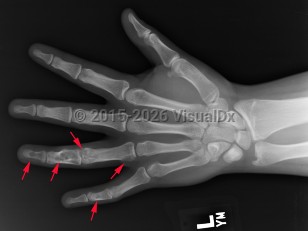

Ollier disease and Maffucci syndrome are nonhereditary conditions that present as multiple enchondromas. Ollier disease involves multiple asymmetric enchondromas of the digits. It is most commonly seen in childhood. These slow-growing tumors usually stop growing after puberty, but masses can create deformity and limb asymmetry. Pathologic fractures may be seen. Ollier disease has a 15%-20% risk for secondary chondrosarcoma.

Pathophysiology: Enchondroma pathophysiology is believed to involve incomplete endochondral ossification in which physeal remnants become entrapped in the medullary cavity of the metaphysis and proliferate. In the hand, enchondromas are typically diagnosed after a pathologic fracture. Elsewhere, they are typically an asymptomatic incidental finding on x-ray or advanced imaging performed for other reasons. Pain is usually due to a nearby abnormality rather than the tumor itself.